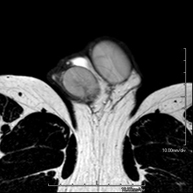

- RM Escrotal (testicular)

Prueba diagnóstica no invasiva que consiste en la obtención de imágenes de alta definición anatómica de la región escrotal mediante el empleo de un campo electromagnético y ondas de radio (con un emisor y un receptor). No utiliza radiación ionizante. En ocasiones se deberá emplear contraste paramagnético (Gadolinio) para completar el estudio. Se utiliza para el estudio detallado de los testículos, para identificar posibles tumores u otras patologías, además de poder visualizar alteraciones de las estructuras adyacentes.